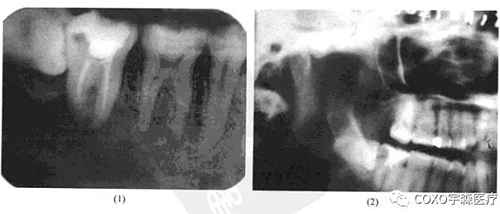

病例 女性,50歲,因[6區(qū)不適在某醫(yī)院攝片發(fā)現(xiàn)6根尖區(qū)有1.5cm×1.5cm陰影而來就診。檢查:[67已行單端固定橋修復(fù),無明顯叩痛與松動(dòng)。下頜全景片示:根尖陰影,周邊整齊,中央有一小游離骨塊狀物。牙片示陰影與[6根尖緊密接觸。疑為[6根尖周炎及局限性死骨形成(圖13-9),拆除[67單端固定橋,發(fā)現(xiàn)[6為活髓,行根管治療術(shù)后,手術(shù)探查,去除病變組織,病理最后診斷為牙骨質(zhì)骨化性纖維瘤。

牙骨質(zhì)骨化纖維瘤臨床上多發(fā)生在牙根部位,不僅有骨小梁形成,而且有牙骨質(zhì)形成,因而將其歸類為牙源性腫瘤。在臨床上并不多見,但其早期僅呈現(xiàn)根尖部頜骨內(nèi)病損時(shí),則易與根尖周病混淆。本病例病灶不大,位于根尖,牙片顯示陰影與[6關(guān)系十分密切,[6有冠修復(fù),但未見行根管治療術(shù),故疑為慢性根尖周炎;由于其中有一小團(tuán)密度與骨質(zhì)相似的鈣化影,故又疑是否為炎癥導(dǎo)致的死骨殘留。然而拆除[67單端固定橋后,發(fā)現(xiàn) 為活髓,就此否定了根尖周炎的診斷。最后經(jīng)手術(shù)證實(shí)為牙骨質(zhì)骨化性纖維瘤。本例的診治經(jīng)驗(yàn)提示:牙骨質(zhì)骨化性纖維瘤早期的 線片可呈不典型表現(xiàn)

(此患者的 線片表現(xiàn)與骨化性骨纖維瘤的多囊、骨質(zhì)鈣化、疏松不一等基本表現(xiàn)完全不一致);為排除根尖周病,牙髓是否有活力存在,也是關(guān)鍵的鑒別點(diǎn)